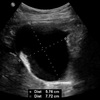

21

Q

A

Cholelithiasis